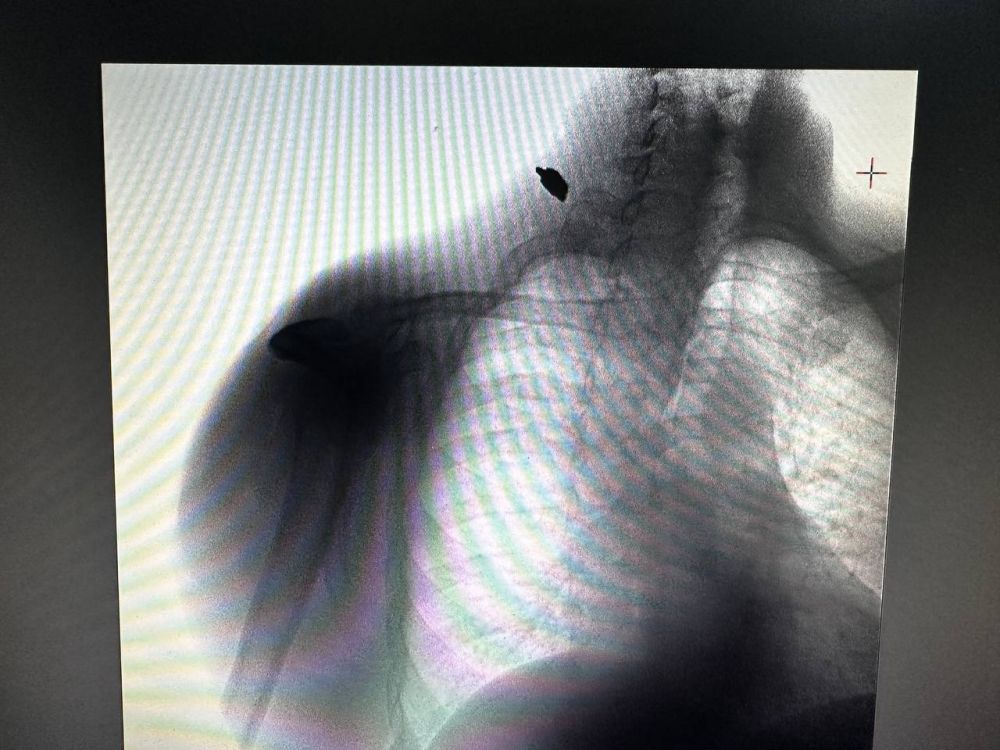

Врачи Федерального медико-биологического агентства России спасли жизнь мужчине с осколочным ранением из Великой ЛепетихиПациент из Великой Лепетихи пострадал в своем собственном дворе во время обстрела со стороны киевского режима....